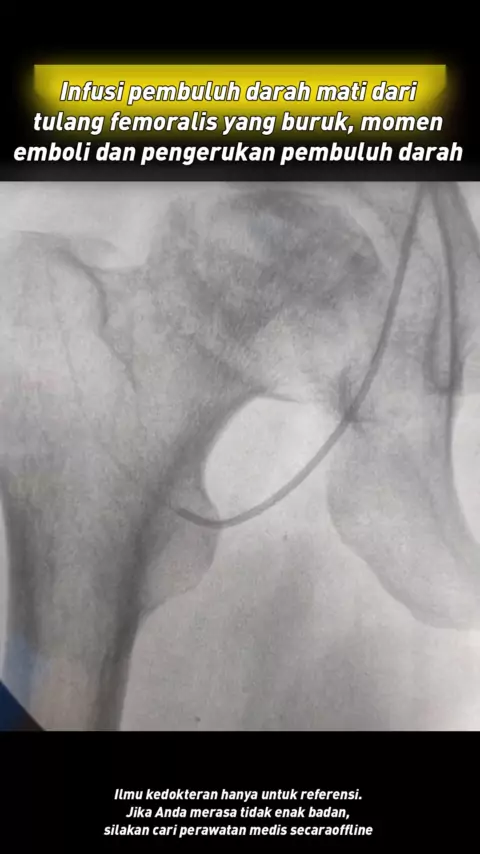

Operasi refusi pembuluh darah kematian femoralis, momen emboli dan pengerukan pembuluh darah # femur bone nekrosis # kesehatan # ilmu kedokteran